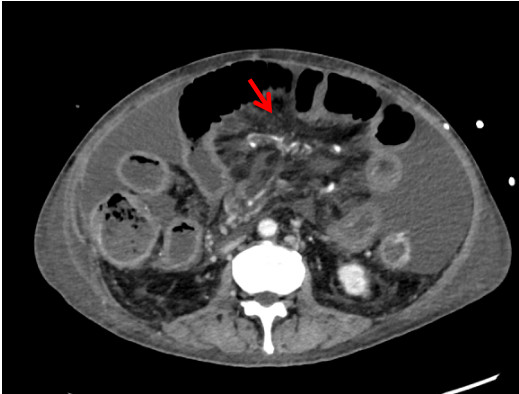

1.2 辅助检查患者神志清,精神软,禁食,睡眠差,发病来体重下降20 kg,体温36.7℃,脉搏67次/min,呼吸16次/min,血压89/56 mmHg (1 mmHg=0.133 kPa)。肺部CT(HR)平扫:两肺散在渗出,两侧胸腔积液伴两肺部分萎陷;腹膜及腹水(彩超):腹腔积液。超声心动图示:左房增大、心律不齐。双下肢静脉彩色多普勒超声:双下肢深静脉血流通畅。肠系膜动静脉CTA:肠系膜上静脉显示欠清,其属支血栓形成考虑(图 1)。系膜网膜模糊浑浊,腹盆腔积液,胃肠壁稍水肿。腹膜后、肠系膜区多发淋巴结稍大,腹盆壁皮下水肿(图 2)。

| 图 2 患者入院时系膜网膜模糊浑浊、盆腔积液 |